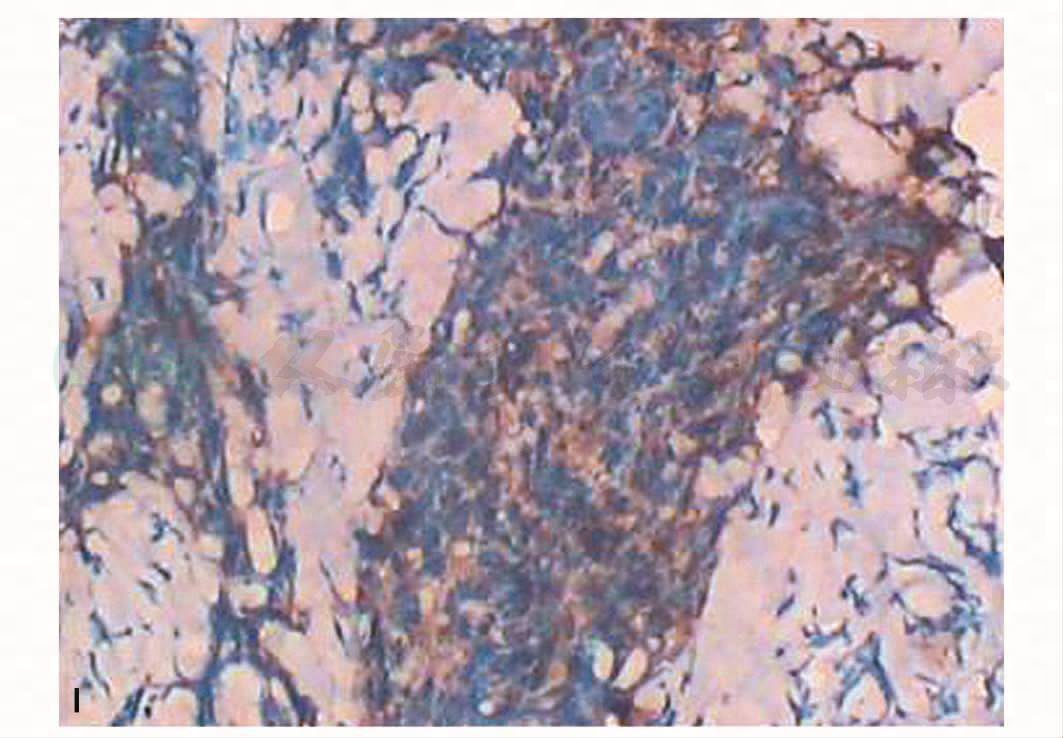

左眼眶0.2~0.3cm组织两粒,镜下组织挤压明显,纤维组织增生,其内见小灶似有异型的上皮细胞,结合临床病史,考虑转移癌。免疫组织化学:CK(+),LCA(-),EMA(+),S-100(-),Syn(-),CgA(-),HMB45(-)。鼻咽0.2~0.3cm组织4粒,镜下为非角化性癌(未分化型),免疫组织化学:LCA(-),CK(+)(图1I、J)。

图1 左侧眼眶转移瘤

A.CT增强扫描;B.T1WI横断位;C.T2WI横断面;D.MR增强横断面;E.MR增强冠状面;F.鼻咽T2WI横断面;G.颅底T1WI横断面;H.病理(HE×100);I.免疫组化CK(+)